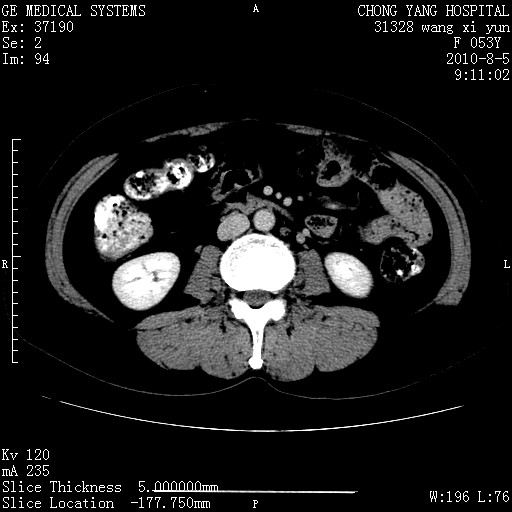

标题: CT28214:F41Y 血尿二十天,建议盆腔平扫加增强。

胆管细胞ca?

1)考虑肝左叶胆管细胞癌。2)脂肪肝。

支持胆管细胞ca。